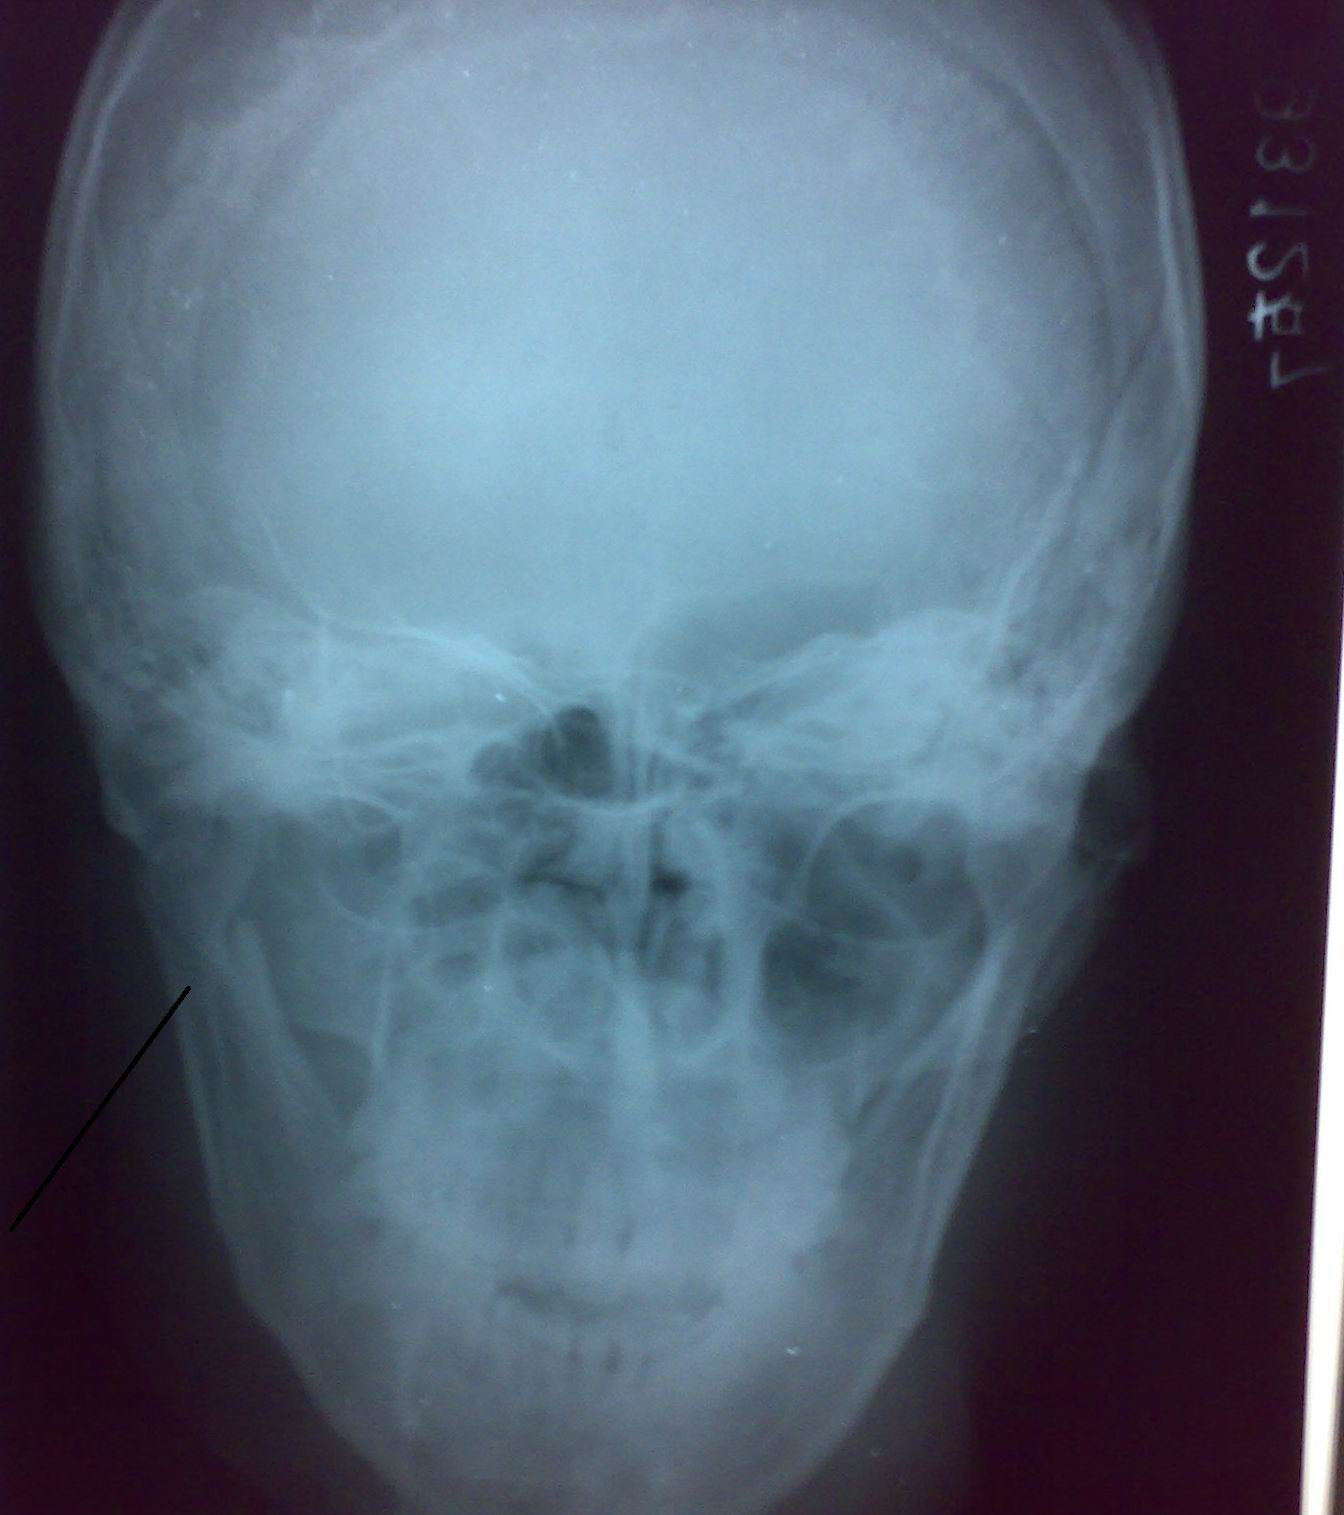

男,28岁,开车时右侧脸撞到方向盘上,病人照完后马上回去了,所以没有加照别的位置,黑线指的左侧地方是有问题还是体位造成的?

颧骨骨折

考虑体位所致。如有髁状突骨折当时并人就应该感觉到,不会照完不等结果就回去的。

未见明确骨折改变(体位不正),如有怀疑,取报告时建议作进一不检查。

是冠突影吧

右下颌骨髁状突下颌升支骨折

考虑右下颌骨升支近髁状突骨折; 建议行ct扫描检查。

髁突重叠影

考虑跟体位不正有关,必要时可以做个ct明确

未见明确骨折改变(体位不正),如有怀疑,取报告时认真询问检查一下,如不能完全排除骨折 建议作进一部检查。

一个ct检查就解决了这个问题

右侧脸撞到方向盘上?这侧是左侧呀。

如果髁状突下颌升支骨折,患者临床症状应该很明显。考虑跟体位有关。